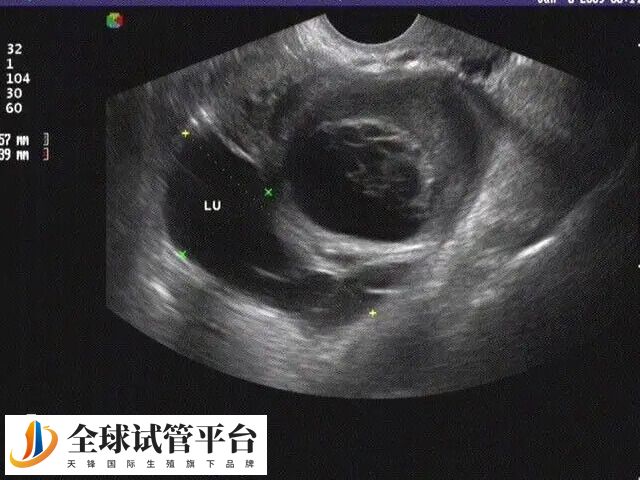

输卵管主要作用是运输。运输卵子、运输精子,及受精卵。卵巢排出的卵子,要经过输卵管和精子汇合,输卵管发生不通现象,精子卵子不能正常结合,受精卵无法形成,自然会影响怀孕。女性出现输卵管不通什么原因呢?